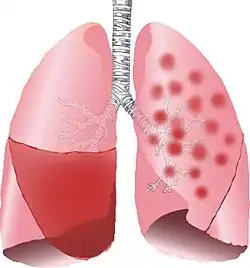

| Typical distribution of lobar pneumonia (left in image) and bronchopneumonia (right in image) | |

It is often contrasted with lobar pneumonia; but, in clinical practice, the types are difficult to apply, as the patterns usually overlap.[2] Bronchopneumonia (lobular) often leads to lobar pneumonia as the infection progresses. The same organism may cause one type of pneumonia in one patient, and another in a different patient.

On gross pathology there are typically multiple foci of consolidation present in the basal lobes of the human lung, often bilateral. These lesions are 2–4 cm in diameter, grey-yellow, dry, often centered on a bronchiole, poorly delimited, and with the tendency to confluence, especially in children.